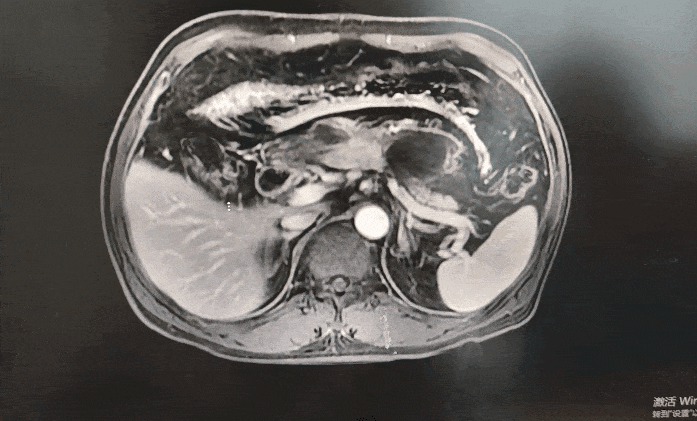

◈ 2023-3-9 上腹部MR增强扫描,对比2023-1-19上腹部MR:胰周多发囊性病变,考虑为术后改变(活检后),假性囊肿形成可能,较前吸收缩小;肠系膜上动脉、腹腔干近段及局部分支周围软组织影,较前缩小,研究者评估整体疗效为部分缓解(PR)。

2023-3-9上腹部MR增强扫描—TTFields联合化疗治疗五月余